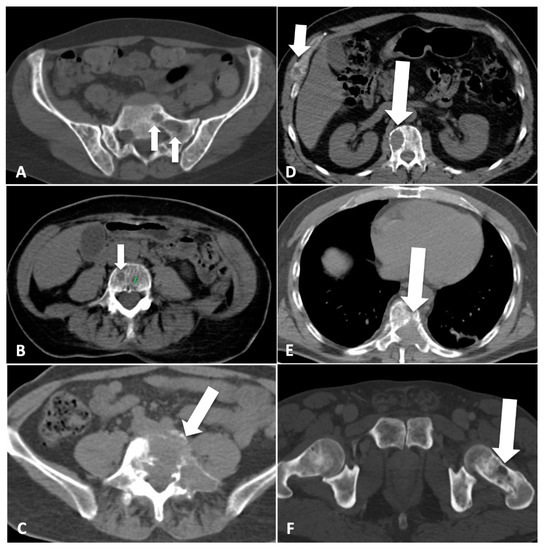

2.2. CT Imaging Atlas

3.1. CT Imaging Atlas